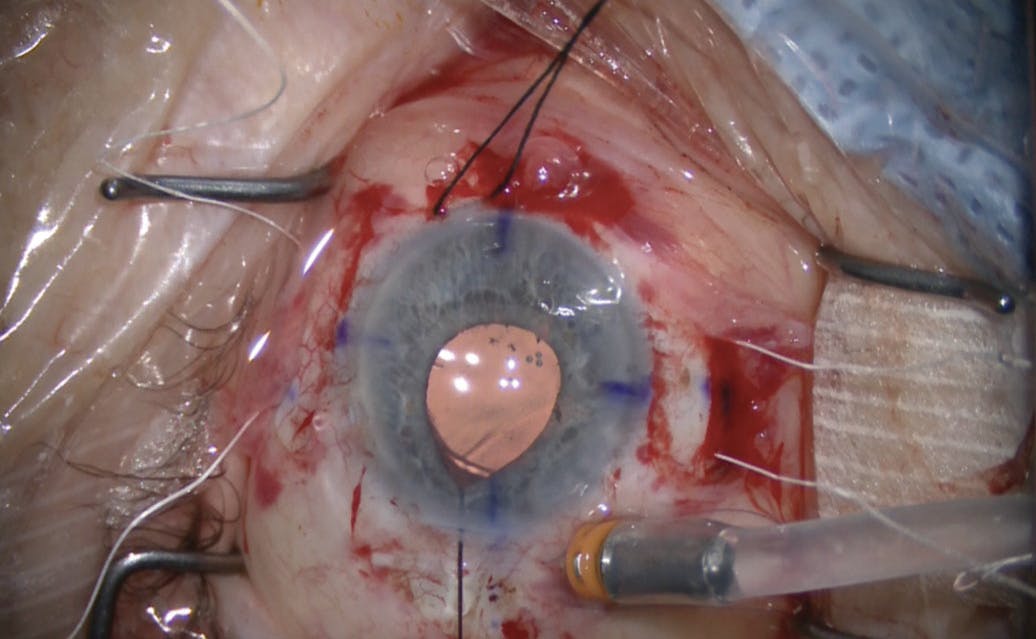

SECONDARY IOL SELECTION AND FIXATION

After explantation of the original IOL, an enVista Toric MX60ET IOL (Bausch + Lomb), selected to address the patient’s high corneal astigmatism, was implanted using pars plana fixation (Figure 4; off-label use). There are case reports of UGH syndrome with this lens platform and approach,6 but we suspect the incidents were due to overly anterior suture fixation of the IOL. We recommend placing the sutures 3 mm posterior to the limbus, rather than the more conventional 2 mm, to minimize the risk of continued contact between the iris and ciliary body. In our experience, a stable, posteriorly fixated optic that avoids such contact is a key determinant of success in these eyes.

Figure 4. Postoperative appearance of a posteriorly sutured toric IOL showed excellent centration and clearance from the iris.